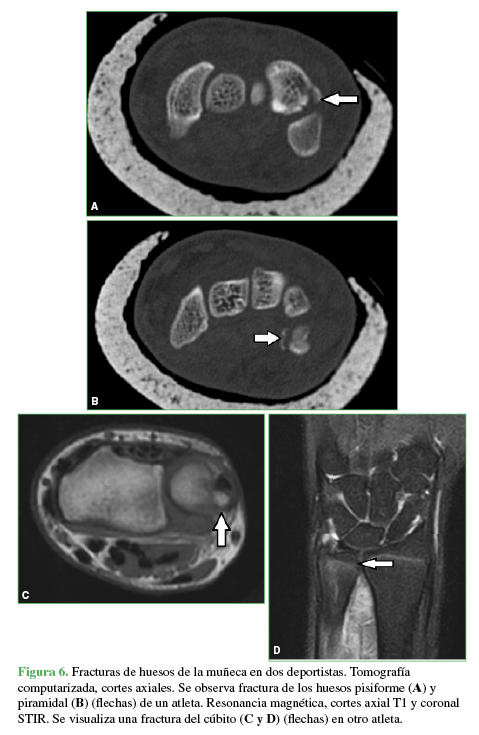

Las distintas patologías informadas se muestran en la Tabla 6 y las Figuras 6,7,8,9,10,11 y 12.

Se observa fractura de los huesos pisiforme (A) y piramidal (B) (flechas) de un atleta. Resonancia magnética, cortes axial T1 y coronal STIR. Se visualiza una fractura del cúbito (C y B) (flechas) en otro atleta.